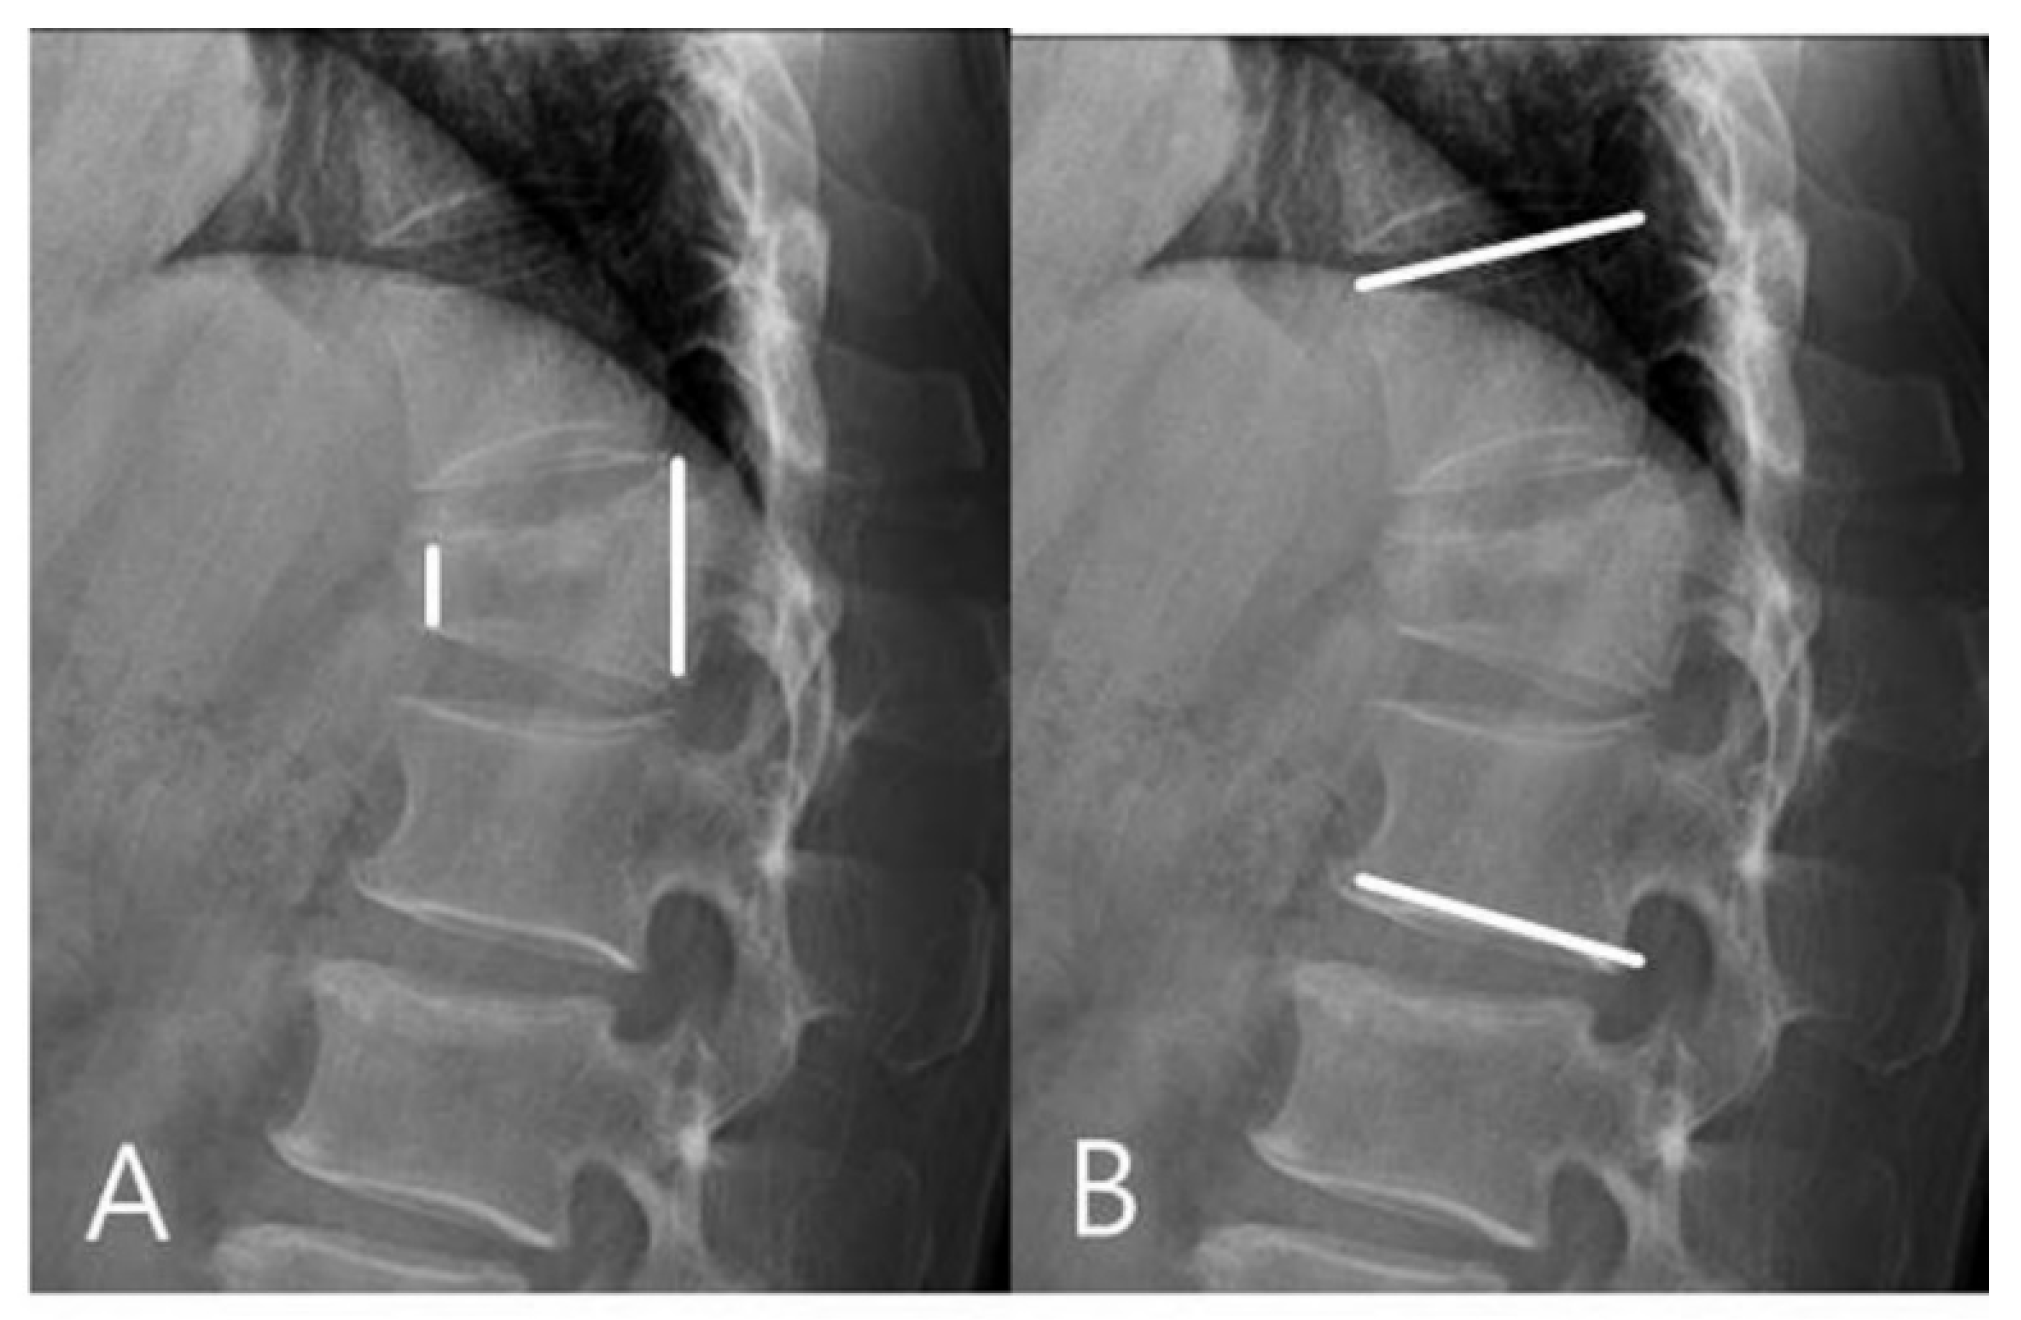

2.3. Radiologic Evaluation and Clinical Assessments

3.1. Radiographic Outcomes